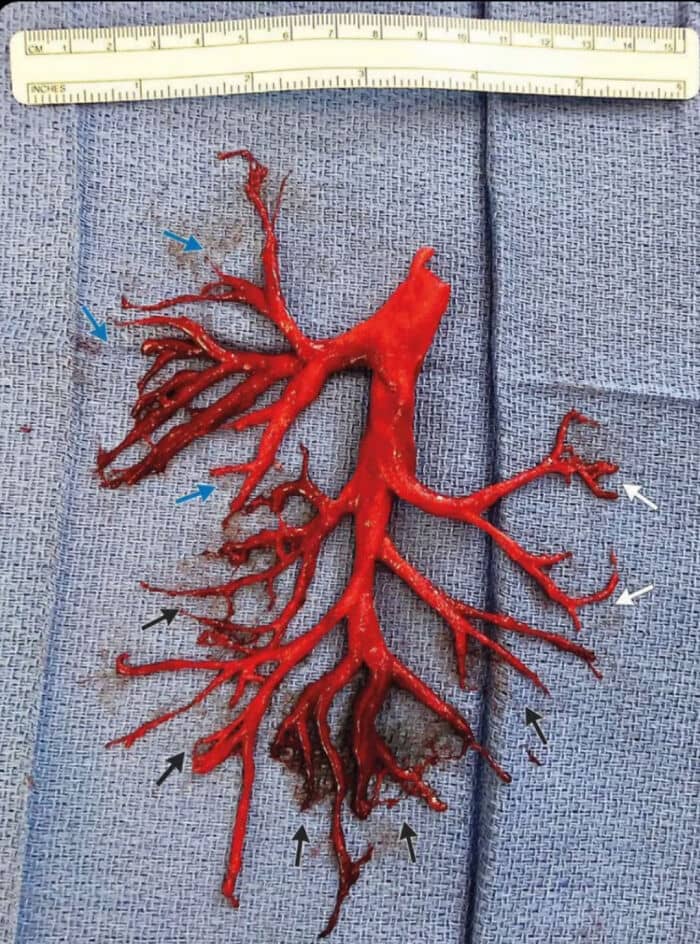

#11 A Blood Clot Coughed Up By Patient That Perfectly Shaped The Lung’s Cavity It Filled